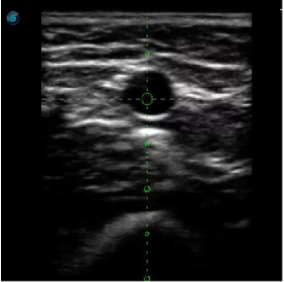

1生殖專(zhuān)用探頭

傳統(tǒng)腔內(nèi)探頭采用直柄設(shè)計(jì),在搭配穿刺架使用時(shí),手術(shù)空間小,不易操作;生殖專(zhuān)用的曲柄探頭,探頭柄采用彎曲成角度設(shè)計(jì),可實(shí)現(xiàn)監(jiān)視、取卵兩不誤,搭載穿刺架時(shí),可以清晰顯示穿刺針的進(jìn)針過(guò)程、深度和位置,實(shí)時(shí)監(jiān)視取卵全過(guò)程,保障取卵操作精準(zhǔn)與安全。

取卵臨床圖